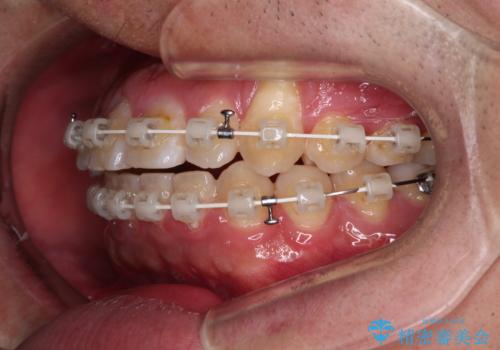

- 矯正装置

- 審美装置

治療装置については、自己管理が煩わしいとのことで、マウスピースではなく目立ちにくいワイヤー装置を選択されました。

また、治療期間中のプラークコントロールが悪く、ブラッシング指導も奏功しなかったため、装置の周りが脱灰した状態(初期むし歯)となってしまいました。